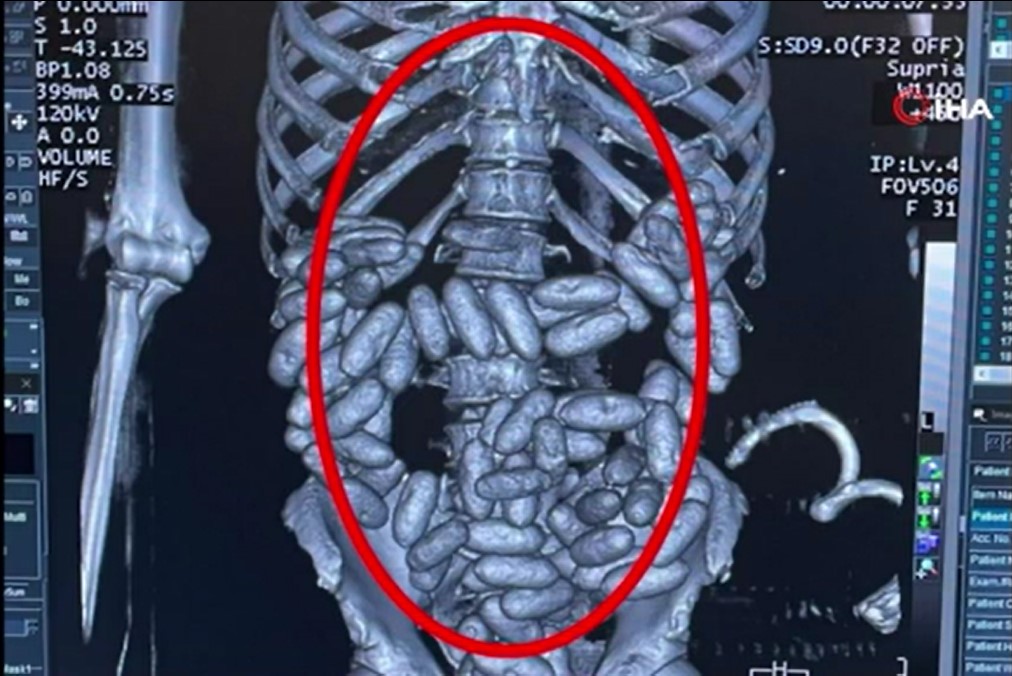

Şüpheli tavırları dikkat çeken B.E.O.’nun midesinde uyuşturucu olabileceği ihtimali üzerine hastaneye götürüldü. Götürüldüğü hastanede yapılan incelemede B.E.O.’nun sindirim sisteminde 96 kapsül içinde 1 kilo 844 gram kokain tespit edildi.